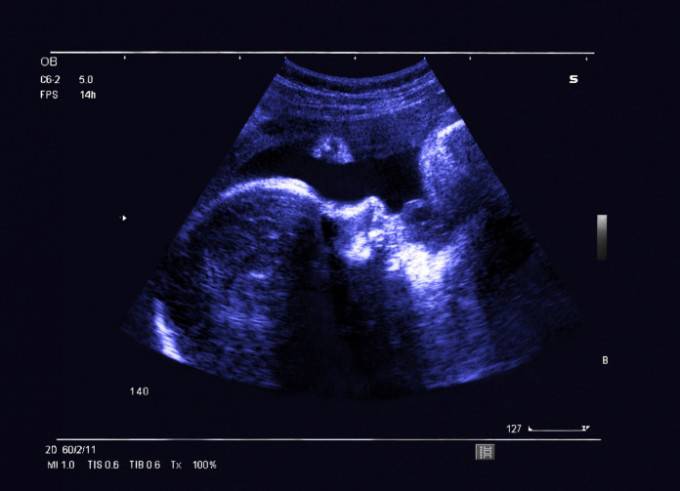

Rapporto tra numero di maschi e femmine dal concepimento alla nascita

Tutti questi dati hanno consentito agli scienziati di ricostruire il rapporto tra numero di maschi e femmine dal momento del concepimento fino alla nascita.